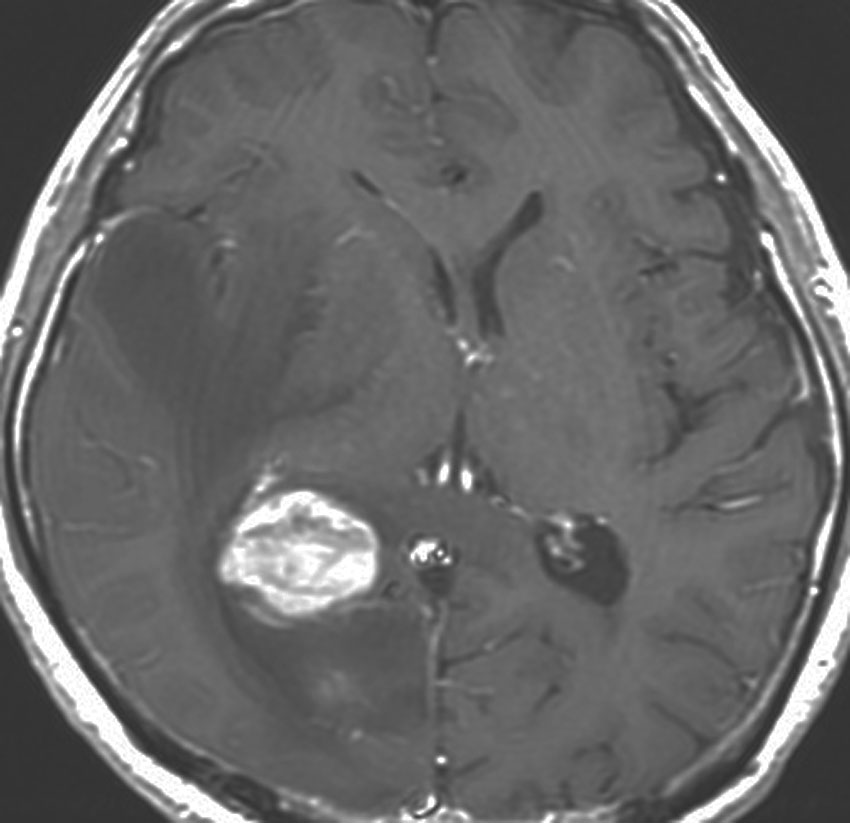

若い患者さんのリンパ腫です。左が診断時MRIで,黄色の矢印でみれる3ヶ所に同時にリンパ腫が発生しています。定位生検術後にすぐにMTX化学療法を3コースしたら,真ん中の画像になりました。ほとんど消失しているのですが,矢印の先にぼーっと少し残っているのでCR(消失)とはいいません。化学療法を終えた後に全脳照射30グレイをしたら右の画像になり治りました。これは順調な治療経過の例です。